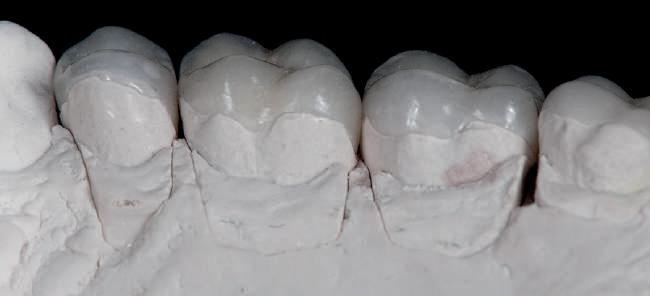

Cazul (1): Reprepararea intraorală a bonturilor Figurile

1. Aspect după inserarea primului set de bonturi implantare individualizate.

2. După 7 luni, bonturile individualizate din prima etapă au prezentat recesie de 1-3mm.

3. Bonturile repreparate intraoral.

Alt caz (1) Figurile

4. După osteointegrarea implantului 2.4., s-a observat recesia în etapa de amprentare a implantului 2.5.; s-a decis reprepararea marginilor bontului individualizat CAD/CAM 2.4. Înainte de preparare s-a aplicat şnur de retracţie pentru a evita lezarea ţesutului şi a îmbunătăţi vizibilitatea dintelui 2.3. şi a marginii bontului implantar individualizat. Aşa cum era de aşteptat, recesia a fost mai mare de-a lungul versantului distal al bontului 2.4. adiacent locului de extracţie vindecat/cu implantul mai nou.

5. Bontul individualizat aplicat (2.5.) cu bontul repreparat anterior (2.4.). Nu a survenit recesie nouă de o perioadă de peste 3 ani.